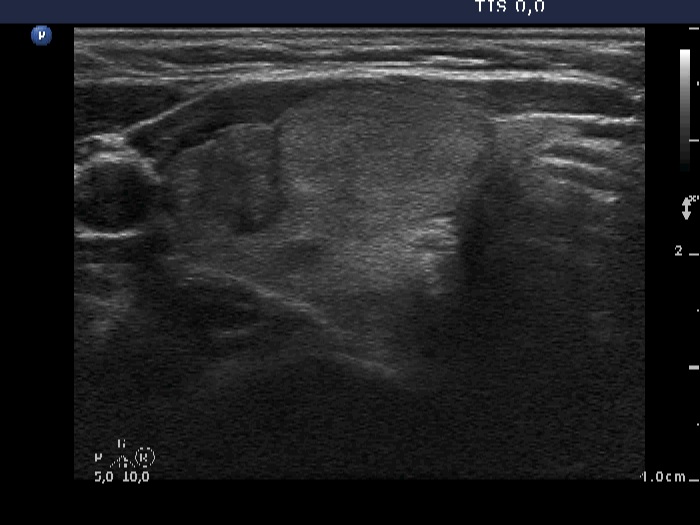

Ultrasonography. The thyroid was echonormal. There were multiple moderately hypoechogenic lesions in the right lobe. The palpable nodule was echonormal and presented halo sign and perinodular blood flow.